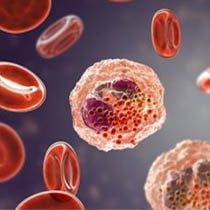

Leading you to better health

Our Services